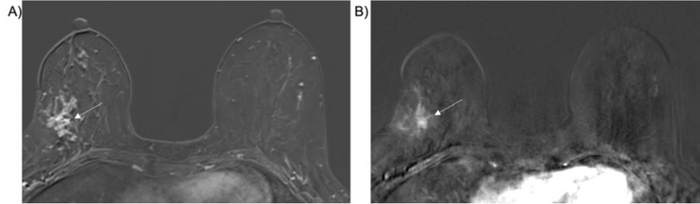

52-year-old woman with stereotactic biopsy-proven intermediate grade DCIS, upgraded to high-grade invasive ducal carcinoma

image: A) Preoperative breast MRI, initial DCE post-contrast axial fat-saturated T1 axial subtraction image, demonstrates 6 cm clumped enhancement surrounding biopsy clip (arrow). B) Ultrafast imaging, post-contrast subtraction with TTE of 5 seconds (arrow) view more